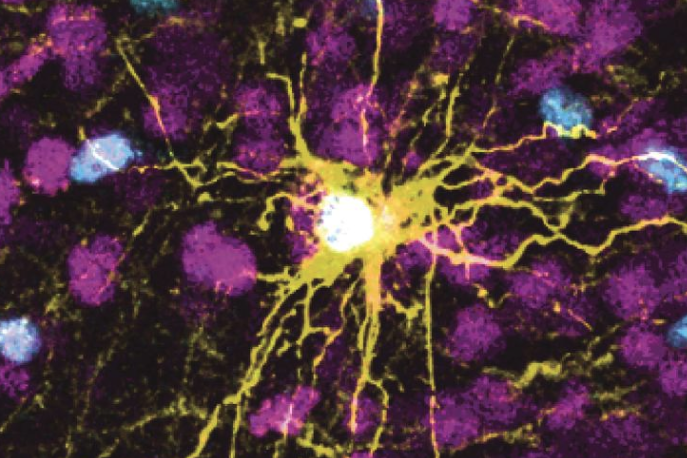

Los científicos han trasplantado células cerebrales humanas en cerebros de ratas bebés, donde las células crecieron y formaron conexiones.

Los científicos trasplantaron esos organoides en crías de rata de dos a tres días de edad, una etapa en la que aún se están formando las conexiones cerebrales. Los organoides crecieron de tal manera que eventualmente ocuparon un tercio del hemisferio del cerebro de la rata donde fueron implantados. Las neuronas de los organoides formaron conexiones de trabajo con circuitos en el cerebro.

Para examinar un uso práctico de este enfoque, los científicos trasplantaron organoides en ambos lados del cerebro de una rata: uno generado a partir de células de una persona sana y otro a partir de células de una persona con síndrome de Timothy, una condición genética rara asociada con problemas cardíacos y espectro autista trastorno.

Cinco o seis meses después, vieron efectos de la enfermedad relacionados con la actividad de las neuronas. Hubo diferencias en la actividad eléctrica de los dos lados, y las neuronas de la persona con síndrome de Timothy eran mucho más pequeñas y no brotaron tantas extensiones que captan información de las neuronas cercanas.